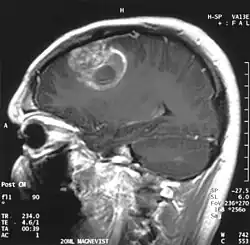

.jpg)

Quando visto através da ressonância magnética, os glioblastomas frequentemente aparecem como lesões com realce em anel. No entanto, esta aparência não é específica, já que outras lesões como abscessos, metástases e esclerose múltipla tumefativa podem ter uma aparência similar.[12]

O diagnóstico definitivo do glioblastoma multiforme requer uma biópsia estereotática ou uma craniotomia com ressecção do tumor e confirmação patológica.